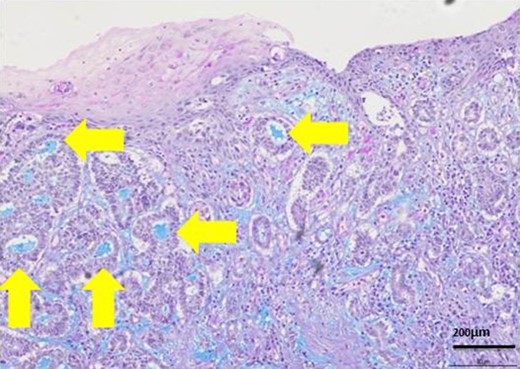

H-E stain revealed that cubical cells which had high nuclear-to-cytoplasmic ratio proliferated with cribriform, tubular or cord-like structure in the dermis and subcutaneous tissue.

The patient was an 83-year-old male with a granulomatous tumor on his left lower leg. He said that it had existed for about 10 years. An incisional skin biopsy was performed at a neighbor medical institution and histopathologically suggested PCACC. He was introduced to our out-patient clinic. At his admission, the tumor was about 4 cm in the diameter and showed a few red granulomatous nodules (Fig. 1). MRI revealed that the tumor infiltrated subcutaneous tissue but did not reach muscle and bone (Fig. 2). The whole-body PET-CT showed that fluorodeoxyglucose (FDG) accumulated at the tumor area of the left lower leg. FDG also accumulated in the left inguen, however any other accumulation was not defected (Fig. 3). Therefore, it was suspected that the left inguinal hot spot was the metastatic lesion from the PCACC lesion at the left lower leg. At the first operation, the tumor was resected 2 cm far from the tumor margin, including basal muscle fascia and periosteum, and the defect was covered with an artificial dermis under general anesthesia (Fig. 4). At the same time, inguinal lymph node dissection was performed. Histopathological examination of the tumor revealed that cubical cells which had high nuclear-to-cytoplasmic ratio proliferated with cribriform, tubular or cord-like structure in the dermis and subcutaneous tissue. Perineural invasion by the tumor was observed. Metastasis to superficial inguinal lymph node was also histological confirmed (Figs 5 and 6). Most lumens had mucus which was stained by Alcian-blue (AL-B) and Periodic acid-Schiff (PAS) inside of them (Fig. 7). In the immunohistochemical findings, the tumor cells were positive for EMA, SMA, S-100protein, BerEP4, p63 and C-kit (Fig. 8). According to these clinical and pathological findings, the tumor was finally diagnosed the tumor as PCACC. Microscopically, the tumor was resected completely.